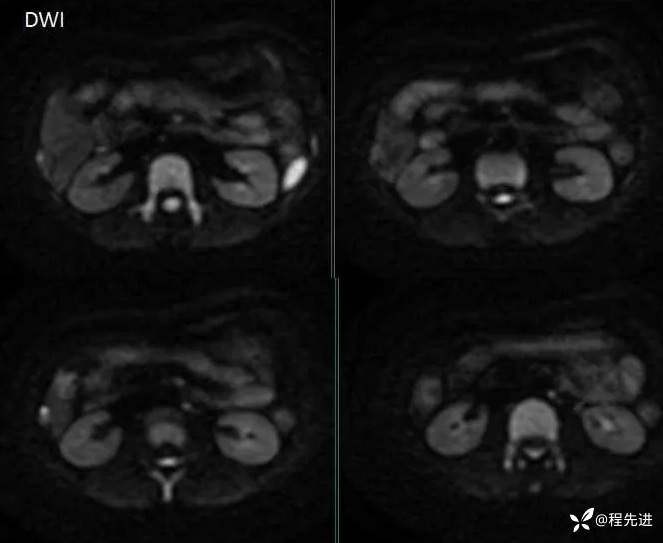

MRI检查: